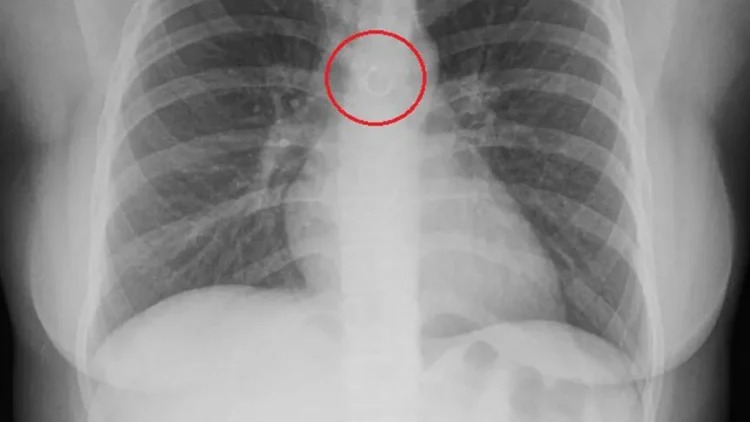

MEXICO CITY: Seorang wanita warga Mexico berusia 26 tahun terkejut besar selepas mendapati batuk berlarutan yang dialaminya berpunca daripada sebentuk subang hidung yang tersangkut di dalam paru-paru. Monica Deyanira Cabrera Barajas mula mengalami masalah batuk berlarutan selama kira-kira sebulan sebelum memutuskan untuk mendapatkan rawatan doktor. Walaupun menjangkakan keputusan pemeriksaan sinar-X (X-ray) akan mendedahkan masalah kesihatan, dia sama sekali tidak menyangka akan menemukan perhiasan hidung miliknya di dalam organ tersebut. Menerusi…